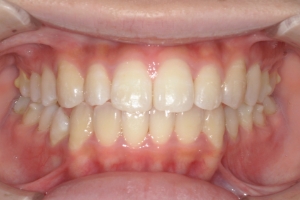

PROCESS

半年

AFTER

治療後

下の前歯が上あごの歯ぐきに当たるほど噛み合わせが深く、そのことが原因で上顎歯列の正中にすき間(正中離開)が生じていました。部分矯正ですき間を無理やり閉じても、噛み合わせが深いままでは治療後の再発リスクが高くなります。そのため全体矯正で奥歯の噛み合わせを整え、噛み合わせを浅くしつつ前歯を並べました。正中離開は戻りやすい傾向があるので、再発を防ぐため固定式リテーナーを推奨しています。